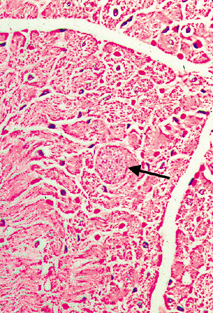

Toxoplasmosis in Immune-Suppressed Patients

Toxoplasma encephalitis (inflammation of the brain) and Toxoplasma myocarditis (inflammation of the heart) are well recognised opportunistic infections in patients who are immune suppressed, particularly in relation to AIDS and chemotherapy for cancer. The Toxoplasma encephalitis has the usual appearance of an encephalitis from any cause, that is, focal areas of death of cerebral tissue associated with a mononuclear inflammatory cell infiltrate. But in addition, Toxoplasma cysts are found in the affected brain tissue.

This figures are from the heart of a middle aged male who died from AIDS. The Toxoplasma cyst is expanding the myocardial muscle fibre. In this case there is no inflammatory reaction associated with the cyst. The presence of an inflammatory reaction is variable.